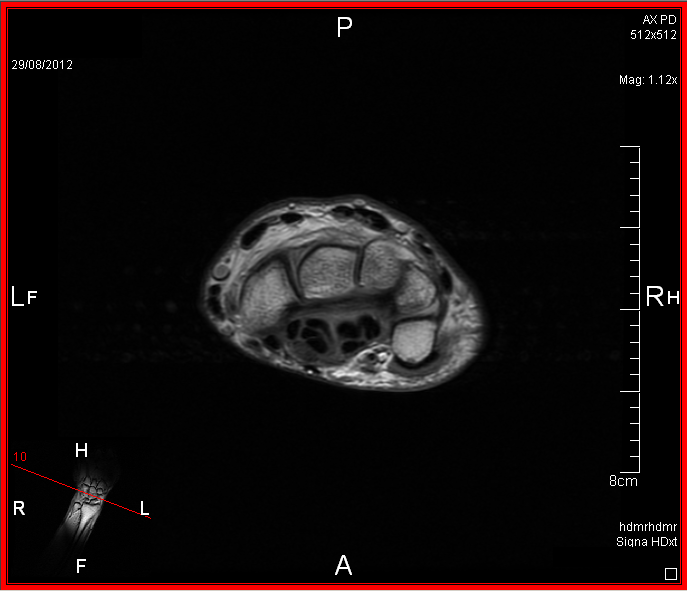

I've posted a few example pics, sadly you need to be an expert to know whats going on as I have no idea. My next appointment with the specialist is late September.